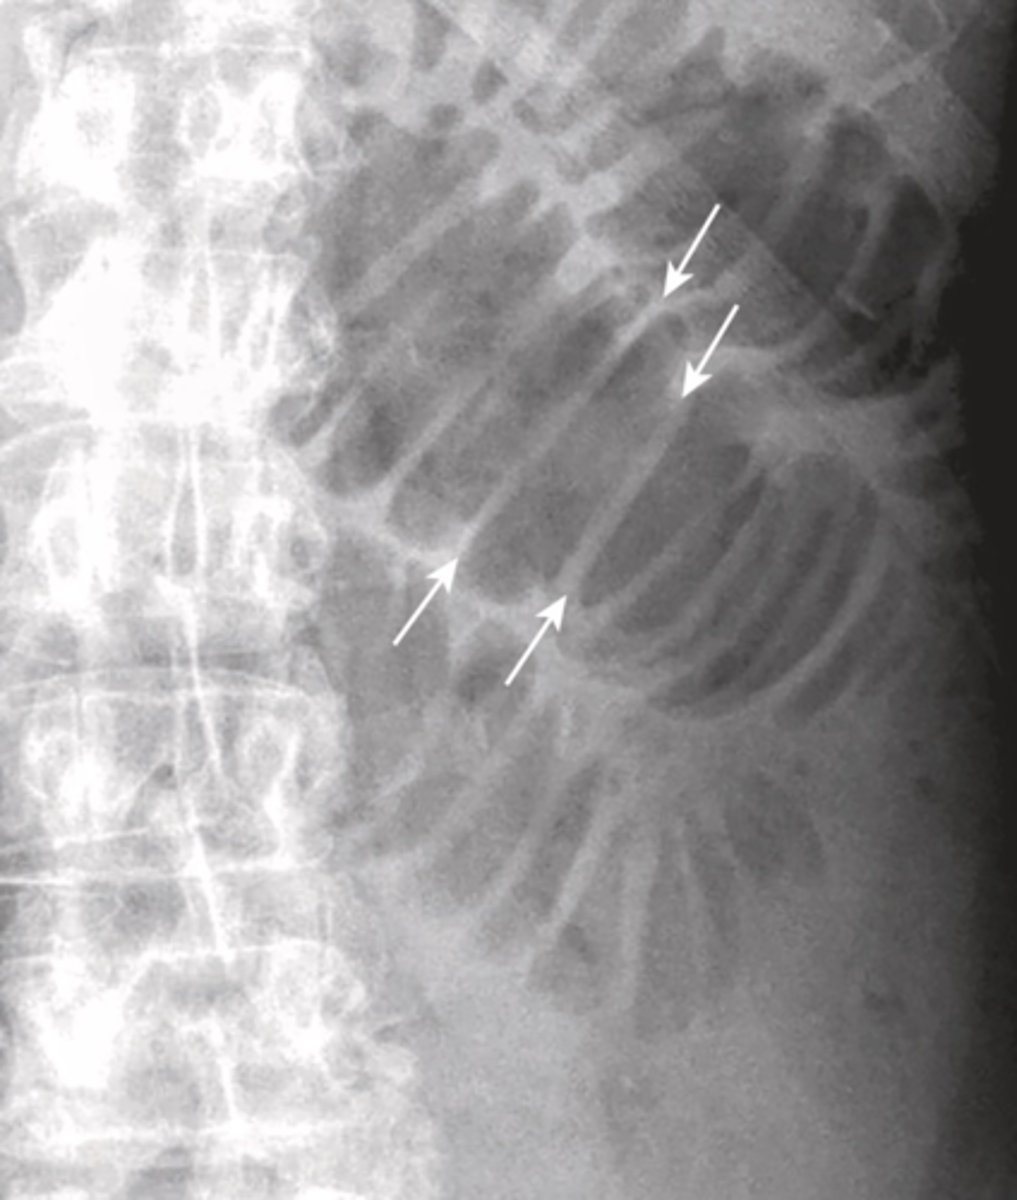

small bowel obstruction

lesion obstructs lumen, proximal to transition point bowel loops become dilated with air, distal to transition point bowel loops become decompressed, no air in rectosigmoid

causes: post-op adhesions, malignancy, hernia, gallstone ileus, intussusception, IBD

SBO imaging

X-Ray shows multiple dilated bowel loops, "step ladder appearance", no or little gas in colon/rectum

CT shows transition point, small-bowel feces sign (proximal to transition intestinal debris and fluid accumulate